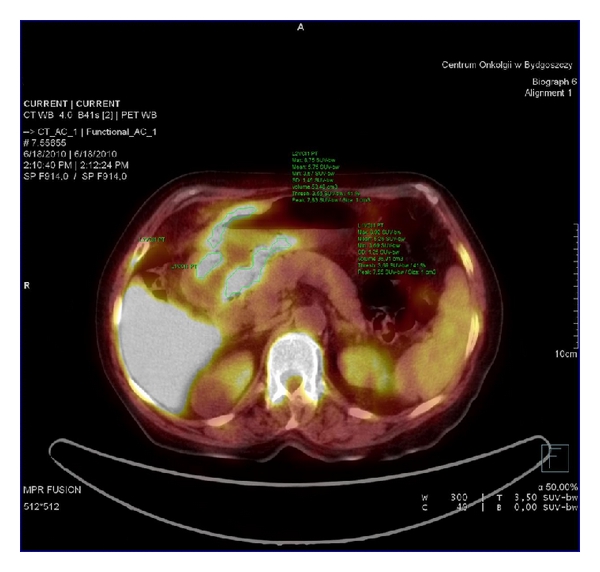

Imaging was performed on the whole-body high-resolution PET/CT scanner Biograph 6. The images were acquired 60 min after administration of MBq of radiotracer. Standard CT scans were undertaken at 120 kV, 100 mAs, and 0.8 s rotation with a 1.25 mm slice width with no contrast injection. Pitch was 0.9. PET data were acquired in 3D mode for 3 min/bed. Acquisition of PET/CT was performed in two steps. Just before acquisition, patient drunk a glass (300 mL) of water to fulfill stomach. First, whole-body CT for attenuation correction and anatomical localization without contrast media was done. Immediately after CT, PET acquisition of two beds of placed on upper and mild abdomen was performed. As we tested before, this acquisition enables showing distended stomach without wall movement. The PET and CT parts of the image were exactly in the same position. Next, (without patient’s position change) whole-body PET was performed. For attenuation correction and localization, the first whole-body CT was used.

To assure the proper interpretation, nuclear medicine and radiology specialists read the examination. They analyzed the image of the stomach using 18F FLT PET/CT and knowledge from gastroscopy. Any discrepancies in the interpretation were solved by consensus. They selected the tumor localization according to the CT. In the tumor, increased focal uptake was detected and assessed by measurements of the maximum standardized uptake value (). The normal stomach wall was chosen in the area of thin stomach wall (CT) and uniform FLT uptake. Then, we assessed the physiological FLT uptake in the stomach wall having knowledge about localization of the cancer from gastroscopy descriptions (files). These areas were omitted in physiological FLT uptake analysis. The images from the first two beds covering only upper abdomen with distended stomach were taken into consideration in this analysis. The ellipsoidal (circular) VOIs with the diameter of 10 mm were placed in the chosen areas which were the most active (the highest uptake) in the areas affected by gastric cancer and free of disease. The from these VOI-s was calculated according to the standard formula (Bq/g × body weight (g)/injected activity in Bq).

In 25 out of 104 patients in the study, the was measured in normal gastric wall. On the basis of endoscopic evaluation and surgical estimation, the gastric wall with no infiltration was chosen (CT), and the was calculated. It has reached mean value and standard deviation of , respectively (from 1.01 to 2.55) (Figure 1). There were no statistical differences in the FLT uptake in normal gastric mucosa related to age. The FLT uptake was significantly lower than that in the cancer tissue (mean —) and the optimal cut-off value differentiating tumor versus nontumor was found at the level of 2.3 (sensitivity—97% and specificity—92%). For the threshold 2.6, the respective values were 94.7% and 100%, but in 5 patients with cancer the was below this value (false negative ratio—5.3%).